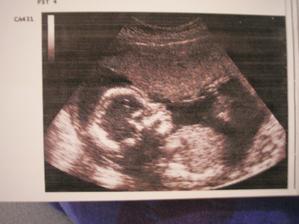

V 32tt nám definitívne potvrdili, že čakáme chlapčeka... čo chlapčeka, riadneho chlapa, lebo odhad hmotnosti je 2400g.

No a v 38tt je to už 4190g!!!

Maroško sa narodil deň pred termínom, teda 14.9.2009 o 9:00 s mierami valibuka - 4850g a 53cm, no aj tak je to "náš malinký".